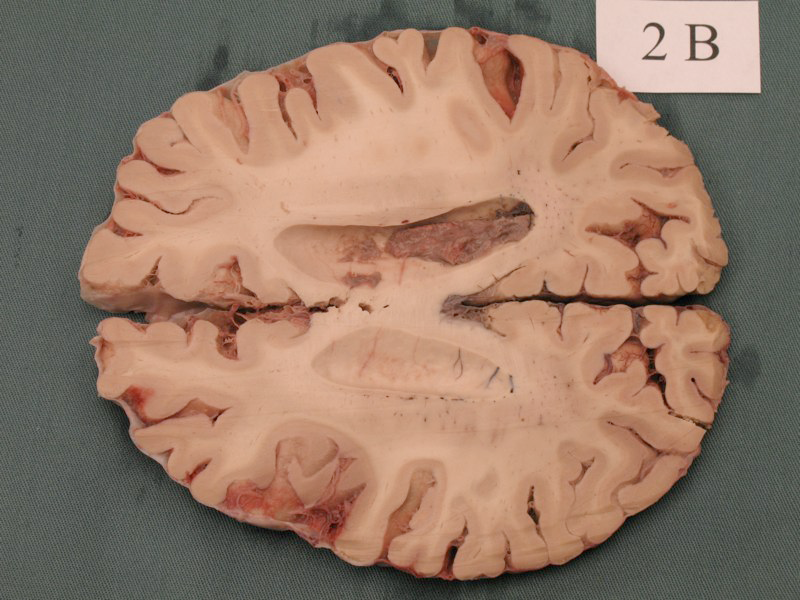

A single mutation can lead to dramatic brain size defects

Mutation in a spindle pole gene call ASPM1 (altered mitosis during brain development)

Bond:2002, see also Neuroscience 5e Fig. 1.1

For example, shown here is a person with a mutation in ASPM1 a protein used to make spindle poles for mitotic stem cells during embryonic development.

But most single gene mutations do not cause such drastic effects, with a more subtle and complex set of genetic and environmental risk factors causing neurological disease, similar to and probably exceeding the complex etiology of cancer.

2cm scale bar. left 13yr old female patient. right 11 yr old control.